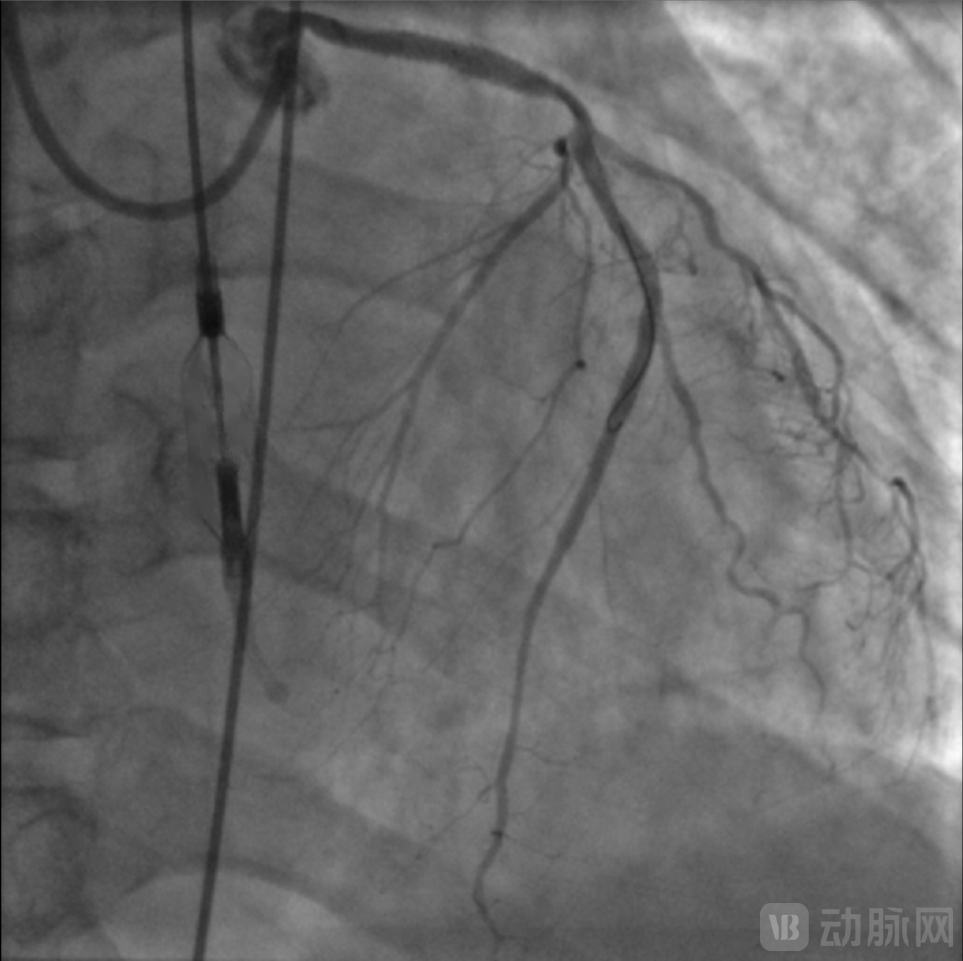

Wolverine(3.5*10mm)切割球囊于左主干病变处扩张,取Bingo(3.5*20mm)药物球囊扩张释放药物,造影见病变扩张满意,无残余狭窄。

复查造影提示支架扩张满意,第一对角支残余狭窄<30%,前降支中段至远段无残余狭窄,TIMI血流3级。手术过程流畅,NyokAssist®操作便捷,过弓、跨瓣性能优异,术中患者血压平稳,心超显示介入泵位置良好稳定,主动脉瓣及二尖瓣未见反流加重。

术后介入泵顺利回撤至鞘内撤出,仅使用单把ProGlide缝合器完成股动脉穿刺处止血,患者6小时后即下床活动,无血管并发症。术后患者恢复良好,血常规、肝肾功能等指标均未见明显异常,术后动脉血压维持在130/80 mmHg,术后心超显示左室射血分数改善至36%,未见主动脉瓣及二尖瓣损伤,2天后患者出院。